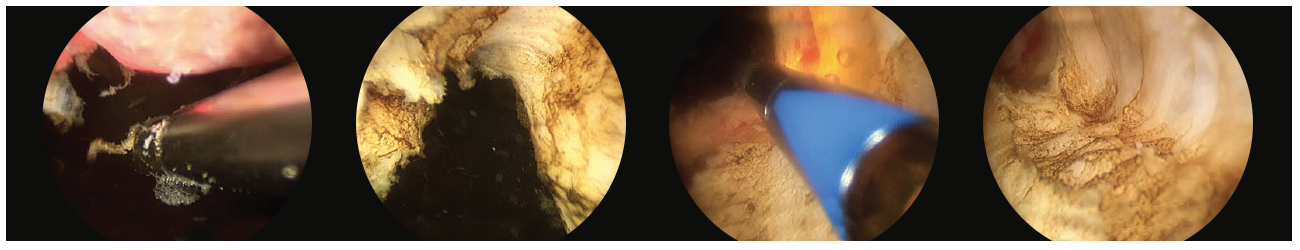

• Then comes the heart of the procedure, in which I systematically debulk the prostate by using the laser to remove the adenoma (non-malignant prostate tissue) off the surgical capsule, pushing tissue pieces that are too large to be vaporized into the bladder. (Fig. 3)

3 scope images. Identifying verumontanum. Figure 3, Part 1: VIT along capsule of floor tissue.

Additional 3 scope images. Identifying verumontanum. Figure 3, Part 2: VIT along capsule of floor tissue.

• This is then repeated for both lateral lobes after a 12 o’clock incision is made through the anterior commissure to the capsule and the lateral adenoma tissue are freed off the capsule. (Fig. 4)

4 scope images. Which are illustrating how to debulk the prostate. Figure 4: Incision and release of left sided adenoma.